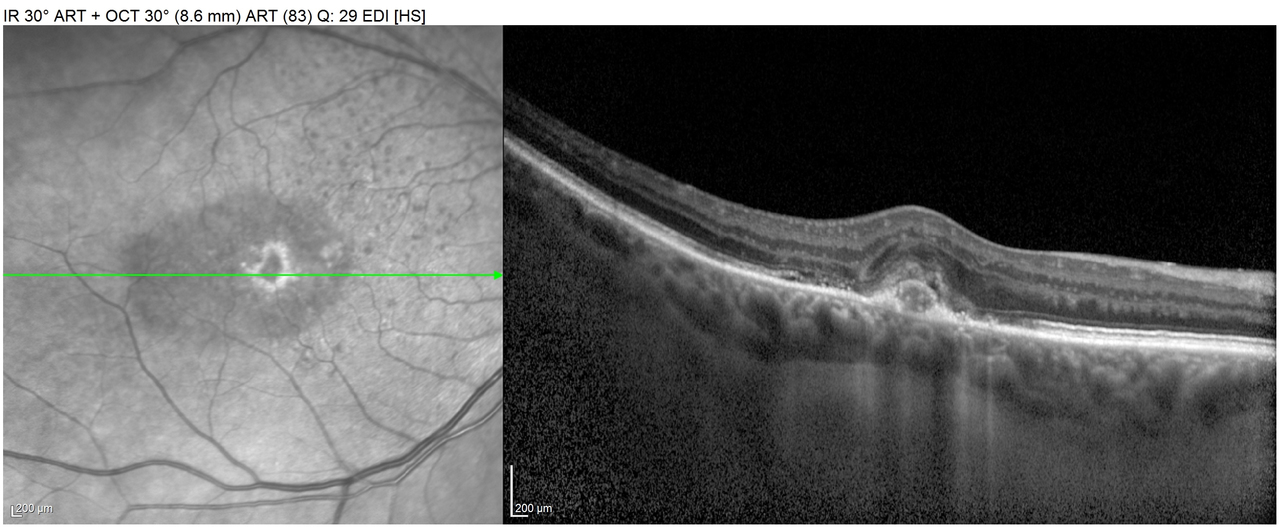

Voici les images des OCT maculaire DROIT

et GAUCHE

Question 5 : Quels signes sont présents sur ces deux OCT maculaire ?

Ici on remarque à DROITE une déformation dans l’épaisseur de la rétine qui correspond au décollement de l’épithélium pigmentaire (ou DEP). En effet le néo-vaisseau d’origine choroïdienne pousse la rétine vers le haut avant de saigner dans un espace anatomique appelé « espace sous rétinien », dont l’origine s’explique par l’embryologie oculaire (je vous renvoie vers vos cours de 2ième année de médecine). Ce soulèvement, qui est donc en dessous de la rétine, entraine un bombement vers le haut de l’épithélium pigmentaire d’où le terme « DEP ». Ensuite le sang de la DMLA exsudative se loge dans l’espace sous rétinien, d’où le terme de « liquide sous rétinien ». Ces signes sont très bien visibles ici. Sur l’œil GAUCHE, il n’y a ni DEP ni liquide sous rétinien, par contre on remarque que déformation rétrofovéolaire qui est en fait un drusen, la lésion AVANT le stade de DMLA.